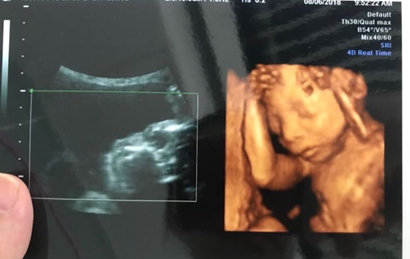

网上流传着很多宝妈做四维彩超检查,医生说是男孩,但是结果生出来是女孩的案例,那么四维彩超男孩翻盘实例有哪些,为什么四维是男孩结果生女孩?

孕22周以上的胎儿各方面器官都已经渐渐成熟,胎儿的四肢以及生殖器官也已经形成,这时候做四维彩超是完全可以看到胎儿的生殖器官,从而判断胎儿的性别。不过也不是每个胎儿都那么配合做四维彩超的,有些胎儿的手刚好挡住关键部位,那么就没办法准确的判断胎儿的性别。

有人反应,做四维彩超的时候,医生明明说了是男孩,但是生出来却是女孩。其实,有些胎儿比较淘气,把手指放在两腿之间,那么做四维彩超的时候,有些医生就误以为是胎儿的生殖器官,然后就判断是男孩,那么生出来就肯定是女孩。所以,做四维彩超的报告单上面也写了,不是百分百准确的,有一定的误差。